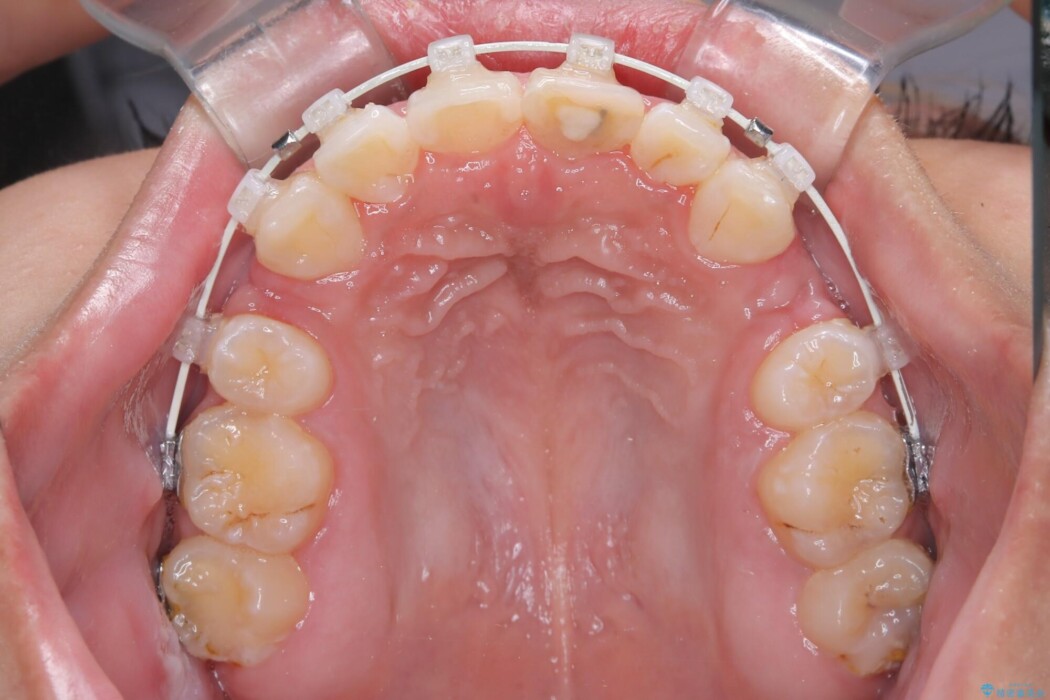

抜歯によって得たスペースを活用し、審美ワイヤーによる繊細な角度調整を行いながら前歯を後方へ移動。

突出していた口元のボリュームを段階的に抑制し、理想的なバランスへと導きました。

機能面では上下の緊密な咬合を確立し、審美面ではEラインの劇的な改善を実現しました。 形態と機能の両立により、患者様の満足度が非常に高い仕上がりとなりました。